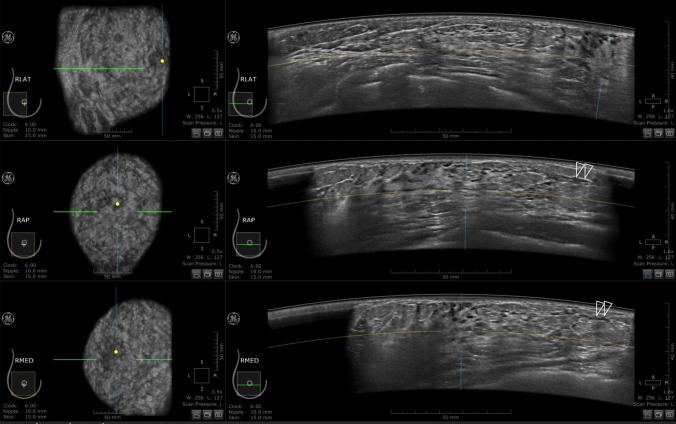

Fig. 1.

Right breast ABUS images of a 29-year-old woman at 20 weeks 5 days of pregnancy. Lateral (LAT), anteroposterior (AP), and medial (MED) images from top to bottom, with a coronal section presented on the left and a horizontal section on the right. These sonograms show ducts extending to the margins of the breast where little echogenic fibroglandular tissue could be seen (double open arrowheads)